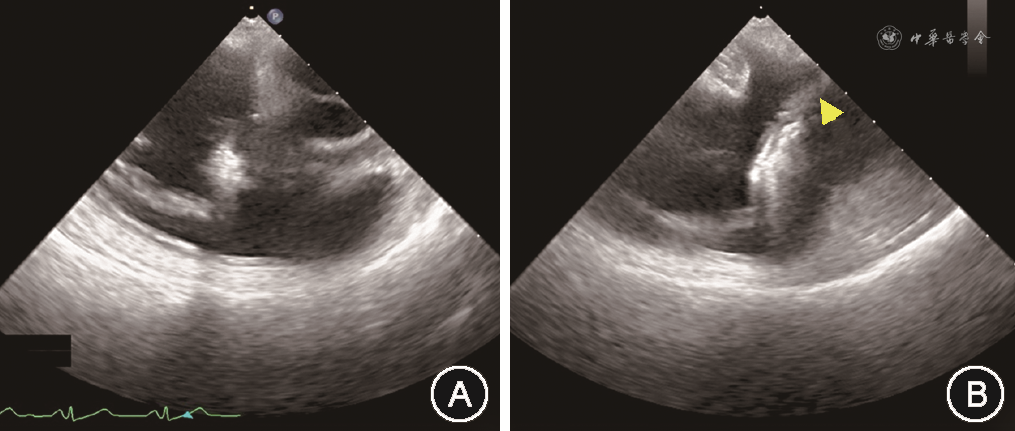

经导管三尖瓣缘对缘修复手术在全身麻醉、气管插管下进行。本研究所使用的经导管三尖瓣缘对缘修复器械为淇麟三尖瓣缘对缘修复系统(上海申淇医疗科技有限公司)、Neoblazar经导管三尖瓣夹合器及输送系统(江苏臻亿医疗科技有限公司)。本文所描述的手术过程以淇麟三尖瓣缘对缘修复系统为例。经右侧股静脉穿刺送入加硬导丝,在TEE 双腔切面引导下将导丝送入上腔静脉。使用18 Fr(1 Fr=0.33 mm)扩张子扩张股静脉穿刺处。将导引鞘头端调直,在TEE Bicaval View引导下沿导丝送入导引鞘使其头端位于右心房中部。若导引鞘头端朝向房间隔,可通过向L方向旋转S/L旋钮,或调整导引鞘+/-旋钮增加头端弯度并逆时针旋转导引鞘,使导引鞘头端远离房间隔(图1)。在体外预先测量导引鞘和夹子输送系统的位置关系,并在夹子输送系统上做标记。将夹子输送系统从导引鞘中送入右心房,在TEE双腔切面引导下送入标记深度,完成导引鞘和输送系统的对位,使夹子头端位于右心房中部。TEE显示右心室流入道/流出道切面及Biplane切面(图2),向F方向旋转夹子输送系统上F/E旋钮,使夹子朝向三尖瓣(图3)。通过旋转导引鞘、调整导引鞘S/L旋钮和输送系统F/E旋钮,使输送系统头端运动轨迹在上述两个TEE切面上都和三尖瓣水平垂直。若夹子输送系统从间隔斜向三尖瓣时,被称为“间隔拥抱”(Septal Hugger)现象(图4),可通过向L方向旋转S/L旋钮并顺时针旋转导引鞘调整。通过向患者头端推送或向脚端回撤整体系统,使夹子输送系统在TEE右心室流入道/流出道切面朝向反流束。打开夹子到120°,旋转夹子输送系统手柄使夹子在TEE经胃底短轴切面垂直于反流处瓣膜对合缘(图5)。关闭夹子,操作夹子输送系统手柄,将夹子送入右心室三尖瓣瓣下,切勿送入过深。打开夹子到120°,再次在TEE经胃底短轴切面确定夹子方向。顺时针旋转或逆时针旋转导引鞘,将使夹子分别靠近三尖瓣隔瓣或前(后)瓣,同时回撤夹子输送系统手柄,用夹子捕获三尖瓣隔瓣或前(后)瓣。通常使用TEE右心室流入道/流出道切面及Biplane切面来显示和引导捕获瓣叶,若此切面图像不能清晰显示夹子是否成功捕获瓣叶,可以通过TEE经胃底短轴切面显示瓣叶活动被夹子限制来判断夹子是否捕获瓣叶(图6)。确定夹子捕获瓣叶后,放下上夹壁(Gripper),缓慢关闭夹子,关闭夹子过程中可通过TEE经胃底短轴切面观察到瓣叶活动受限并随着夹子关闭隔瓣或前(后)瓣聚拢(视频1,TEE显示夹子关闭过程,请扫描文章首页二维码观看)。关闭夹子后,TEE检测三尖瓣反流情况,夹子夹持瓣叶长度,评估是否需要调整夹子位置或因夹持瓣叶长度不足而进行再次夹持,以及是否需要补充额外的夹子。评估满意后按照夹子释放流程释放夹子。

因三尖瓣位于心脏的前方,距离食管较远,且容易受到左心人工瓣膜以及夹子输送系统的声影影响,经食管超声探头位于食管中下段时,有可能不能提供足够清晰的图像显示夹子捕获三尖瓣。将食管超声探头送到胃部,并将食管探头前屈并向患者右侧旋转,在20°~60°范围内调整产生的经胃底短轴切面,避免了左心或输送系统的声影影响,可在一个二维平面同时显示三尖瓣三个瓣叶的结构,在此切面使用Biplane功能,可获得显示三尖瓣前瓣和后瓣的右心室长轴图像,可以辅助判断夹子进入右心室的深度,但不能为夹子捕获瓣叶提供引导。利用经胃底短轴图像进行三维图像重建,再利用Multiview进行图像分割重建,可精准获得和夹子重合的超声切面,显示夹子和瓣叶的关系,可用于引导瓣叶捕获和判断捕获程度(图6)。但因进行Multiview图像重建后,图像清晰度会有明显下降,因此对于重建前的二维超声图像有较高的质量要求。因此,经胃底短轴切面在经导管三尖瓣缘对缘修复手术中诸如夹子位置和方向的调整、瓣叶捕获判断、瓣叶夹持程度的判断等重要步骤中发挥关键作用[20]。如右心严重扩大或存在心脏转位,食管中段切面和经胃底短轴切面均无法提供满足引导要求的图像时,可使用心腔内超声[21]。